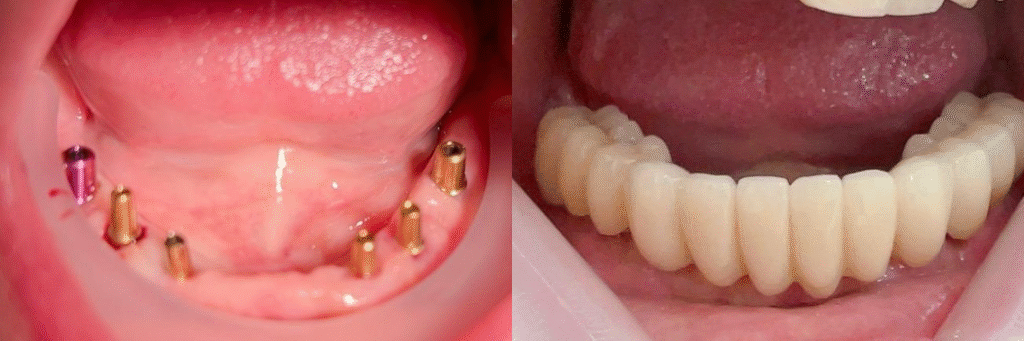

Rehabilitación integral sobre implantes

A small river named Duden flows by their place and supplies it with the necessary regelialia. It is a paradisematic country, in which roasted parts of sentences fly into your mouth. Even the all-powerful Pointing has no control about the blind texts it is an almost orthographic life

One day however a small line of blind text by the name of Lorem Ipsum decided to leave for the far World of Grammar. The Big Oxmox advised her not to do so, because